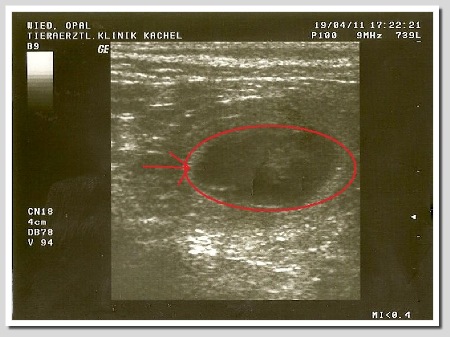

19.04.2011 :

Wir waren beim Ultraschall und siehe da Opal und Butz werden Eltern !!!

Wieviel Babys Opal bekommen wird , dass bleibt ihr Geheimniss !!!

Hier ein paar Ultraschallbilder :